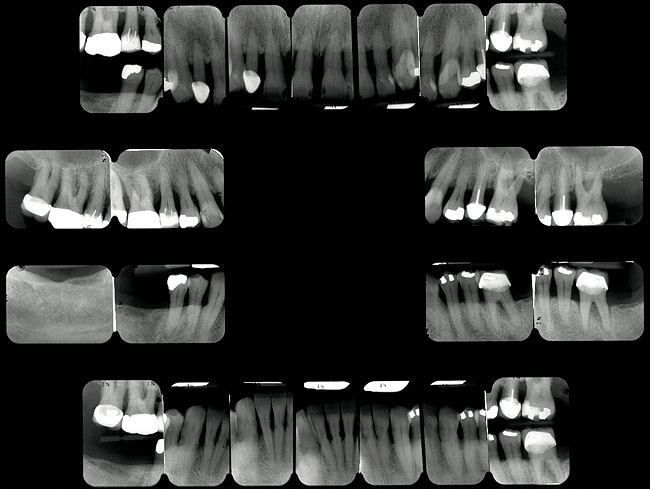

Un pacient în vârstă de 53 ani s-a prezentat cu îngrijorarea majoră privind aspectul, sensibilitatea şi mobilitatea dinţilor săi (fig. 1). El a răspuns pozitiv la chestionarul dentar referitor la sângerarea gingiei, dinţi dureroşi, sensibilitate la temperatură, gustul sau mirosul neplăcut al cavităţii orale, bruxism şi pierderea dinţilor.

Examinarea a evidenţiat adâncimi de sondare generalizate cuprinse între 5-9mm, cu sângerare generalizată şi locaţii cu supuraţie. Combinaţia recesiunii cu adâncimile de sondare a generat o pierdere de ataşament generalizată cu valori între 8-12mm. Radiografiile au evidenţiat pierdere osoasă orizontală severă, defecte osoase verticale multiple şi aspectul unei posibile comunicări parodontale apicale. Aproximativ jumătate dintre dinţi prezentau mobilitate de clasa I, cu dinţii restanţi având o mobilitate de clasa a 2-a şi a 3-a. Toţi molarii manifestau cel puţin o invazie de furcaţie de gradul 1, cu multiple implicări de gradul 2 şi 3. Diagnosticul s-a stabilit a fi AAP tip IV, parodontită avansată.

La examinarea clinică, o serie de dinţi prezentau restaurări directe mici acceptabile. Dinţii de la 1.7. la 1.4., de la 1.2. la 2.6., 3.6. şi 4.5. prezentau fie restaurări directe voluminoase, fie coroane cu acoperire totală, cu un grad ridicat de compromitere structurală. Nu s-au identificat leziuni carioase active. Implicarea pulpară era vizibilă la nivelul molarului 3.6.

Pacientul a relatat o tendinţă ocazională de bruxism. Examinarea a evidenţiat sensibilitatea musculaturii masticatorii şi crepitaţii la nivelul ATM. Era prezentă atriţia minimă la toţi dinţii frontali. Dinţii frontali erau în contact, iar dinţii maxilari frontali era evazaţi şi mobili. Istoricul pacientului privind bruxismul, alături de crepitaţii şi sensibilitatea musculară a contribuit la diagnosticul disfuncţiei ocluzale.

La examinare s-au obiectivat: dinamică labială maxilară crescută, cu afişarea în repaus a 3-4mm din incisivi. La zâmbetul total, marginile gingivale libere nu erau vizibile, datorită recesiunii, dar 2-4mm din structura radiculară era vizibilă dincolo de joncţiunea smalţ-cement (CEJ) la toţi dinţii superiori. Festonul ţesutului moale era apropiat de normal, însă părea neatractiv datorită gradului mare de recesie şi a pierderii papilei. În regiunea frontală inferioară s-a remarcat asimetria orizontală (fig. 2).